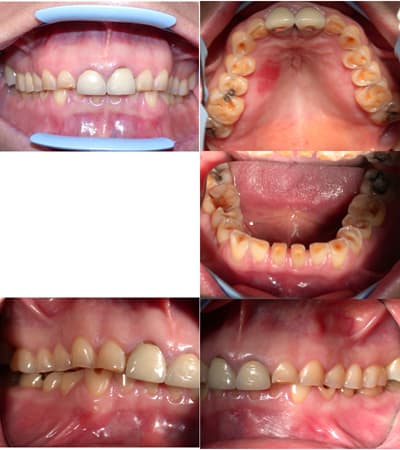

Voici les photos.

La patiente a été soignée à répétition par des composites en technique directe qui finissent toujours par "sauter" puisque l'abrasion de ses dents est de plus en plus importante.

Je pense dans tous les cas lui proposer le port d'une gouttière pour éviter qu'elle continue à tout casser mais j'aimerais vos avis quant au type de reconstruction préférable dans ce cas...